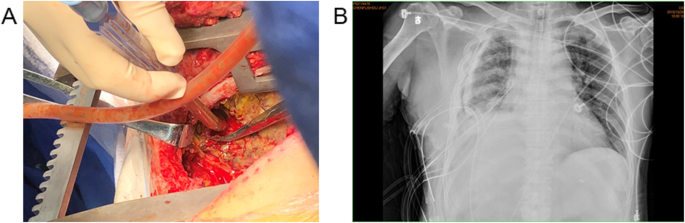

Three months later, the patient suffered from hemoptysis again with about 1000 ml a day. Since conservative treatment failed, the patient agreed to right middle and lower lobectomy by open surgery. During the operation, the middle lobe was found to adhere to the diaphragm. However, when the adhesion was removed, a hole was observed on the diaphragm and colonic perforation was seen. The colon and the diaphragm were closed by suturing separately. Pathology demonstrated bronchogenic cysts with epithelial squamous hyperplasia. In addition, intestinal epithelium was found on the adhesion of middle lobe with diaphragm (Fig. 3). Three days after operation, turbid stool like fluid drained out from the chest tube (Fig. 4), and the patient developed continuous fever and increased white blood cell. Enterogenic empyema was diagnosed and emergent surgery found the diaphragm repair ruptured. Considering the pus was derived from the colon, a jejunostomy and empyema drainage was performed. The pus in the chest cavity was removed and a drainage tube was put into the colon from the chest cavity (Fig. 5). Blood culture grew Staphylococcus aureus, and he received imipenem and piperacillin/tazobartan alternately upon drug sensitive results (Table 2). The right lung re-expanded after surgery and no drainage came out from the colon tube.